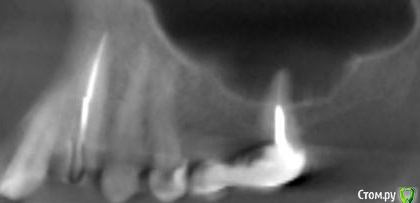

platerx Опубликовано 21 декабря, 2015 Поделиться Опубликовано 21 декабря, 2015 (изменено) Всем доброго времени суток.У меня есть пара вопросов: 1. Что можно сделать с зубом 2.7 История зуба такова:Зуб был сильно разрушен, но мне предложили попробовать пролечить его. Прочистили каналы, я некоторое время ходил с лекарством в зубе. Затем запломбировали каналы и поставили вкладку и коронку (консоль). Это было 2,5 года назад.С тех пор зуб меня иногда немного беспокоил, вызывая некоторый дискомфорт, но я не сильно обращал внимание. В последнее время он стал беспокоить сильнее: время от времени вызывает тянущие и распирающие ощущения, которые усиливаются при нажатии. Слегка побаливает десна и небо с внутренней стороны. Периодически ощущения пропадают. Прикладываю срезы КТ этого зуба. Что можно сделать с этим зубом ? Можно ли извлечь вкладку и перелечить каналы ? 2. При депульпировании зуба 2.4 врач не промывал каналы гипохлоритом (только хлоргексидином), после чего запломбировал их. Это нормально или стоит переделать? На зубе сейчас временная пломба, по прошествии 6 дней зуб не беспокоит. При постукивании есть небольшие неприятные ощущения. Изменено 21 декабря, 2015 пользователем platerx Ссылка на комментарий

DmitrySH Опубликовано 21 декабря, 2015 Поделиться Опубликовано 21 декабря, 2015 Добрый вечер.27. Есть очаг воспаления на одном из корней. Нужно снять коронку, оценить объём тканей. Если все ок, то извлечение вкладки и ревизия каналов.24. Сложно дать однозначный ответ. После выяснения ситуации с 27 планировать имплантацию в области 26 или 26, 27 (если с 27 все плохо) Ссылка на комментарий